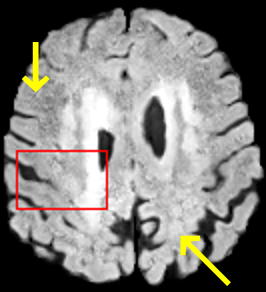

To test the impact of the iterative refinement on YODA’s translation quality, we compared regression and diffusion sampling on the RS data and present additional generation examples in Fig. 6. We observe that diffusion sampling visually resembles the appearance of the acquired images. Regression sampling preserves key anatomical features – the GM/WM boundary, WMHs (Fig. 4), the outline of the pallidum (Fig. 6) – but omits many high-frequency features. To investigate whether iterative refinement during diffusion sampling adds relevant and systematic medical information or only imitates acquisition noise, we performed ExpA sampling, i.e. averaging the output of several ( or ) diffusion trajectories. We observed a gradual loss of high-frequency details when increasing the (see also the supplementary video), indicating that the effect of the iterative refinement is non-systematic. For , the images are visually almost indistinguishable from the initial regression solution (see the supplementary video, and Fig.4 and 6). We directly compared the synthesis results of ExpA () and regression sampling quantitatively and found the differences to be minimal (SSIM: 99.73%, PSNR: 45.30 dB), i.e. diffusion sampling approaches the initial regression solution for a high . The quantitative analysis of the image quality (Tab. 1) showed that diffusion sampling impairs the assessed SSIM and PSNR in comparison to regression sampling for both the in- and external test sets, which we attribute to noise generation (Sec. 3.1). In turn, ExpA averages improved both metrics and, for , performed mostly on par with the regression solution in both test sets in terms of SSIM, while the PSNR in the RS was slightly increased (Tab. 1). However, we observed that ExpA sampling YODA improves the replication of systematic 3D low-frequency image intensity drifts (bias fields) due to the 3D synchronization in 2.5D diffusion sampling. Yet, this apparent advantage did not generalize to the external MBB dataset, as bias fields are MR protocol-specific.

We evaluated the impact of the proposed sampling methods on the performance of the independent, externally trained SHIVA-WMH tool as compared to manual reference labels (Tab. 1). Smoother images (higher or from regression sampling) yielded improved performance over those from diffusion sampling.

To assess the suitability of YODA-generated images for WMH detection independent of segmentation tools, we also calculated the CNR (15) of WMHs. This confirmed that the contrast of WMHs is preserved in the regression images, whereas we noted slightly reduced WMH contrast for diffusion and ExpA-sampled images (Tab. 1).

When analyzing the RS synthesis results (Fig. 4), we noted that most reference methods strive to imitate realistic images, but several artifacts can be observed such as hallucinated WMHs (SynDiff) and salt-and-pepper noise (SynDiff, I2I-Mamba, ResViT).

However, we observed some missing small WMHs (third row, Fig. 9) in the synthetic FLAIR images. Due to the weak input signal, translating small WMHs in inherently difficult and, thus, omitting these WMHs can be seen as conservative. In contrast, a more speculative translation bears the risk of false-positive, hallucinated WMHs (compare e.g., SynDiff, Fig. 4).